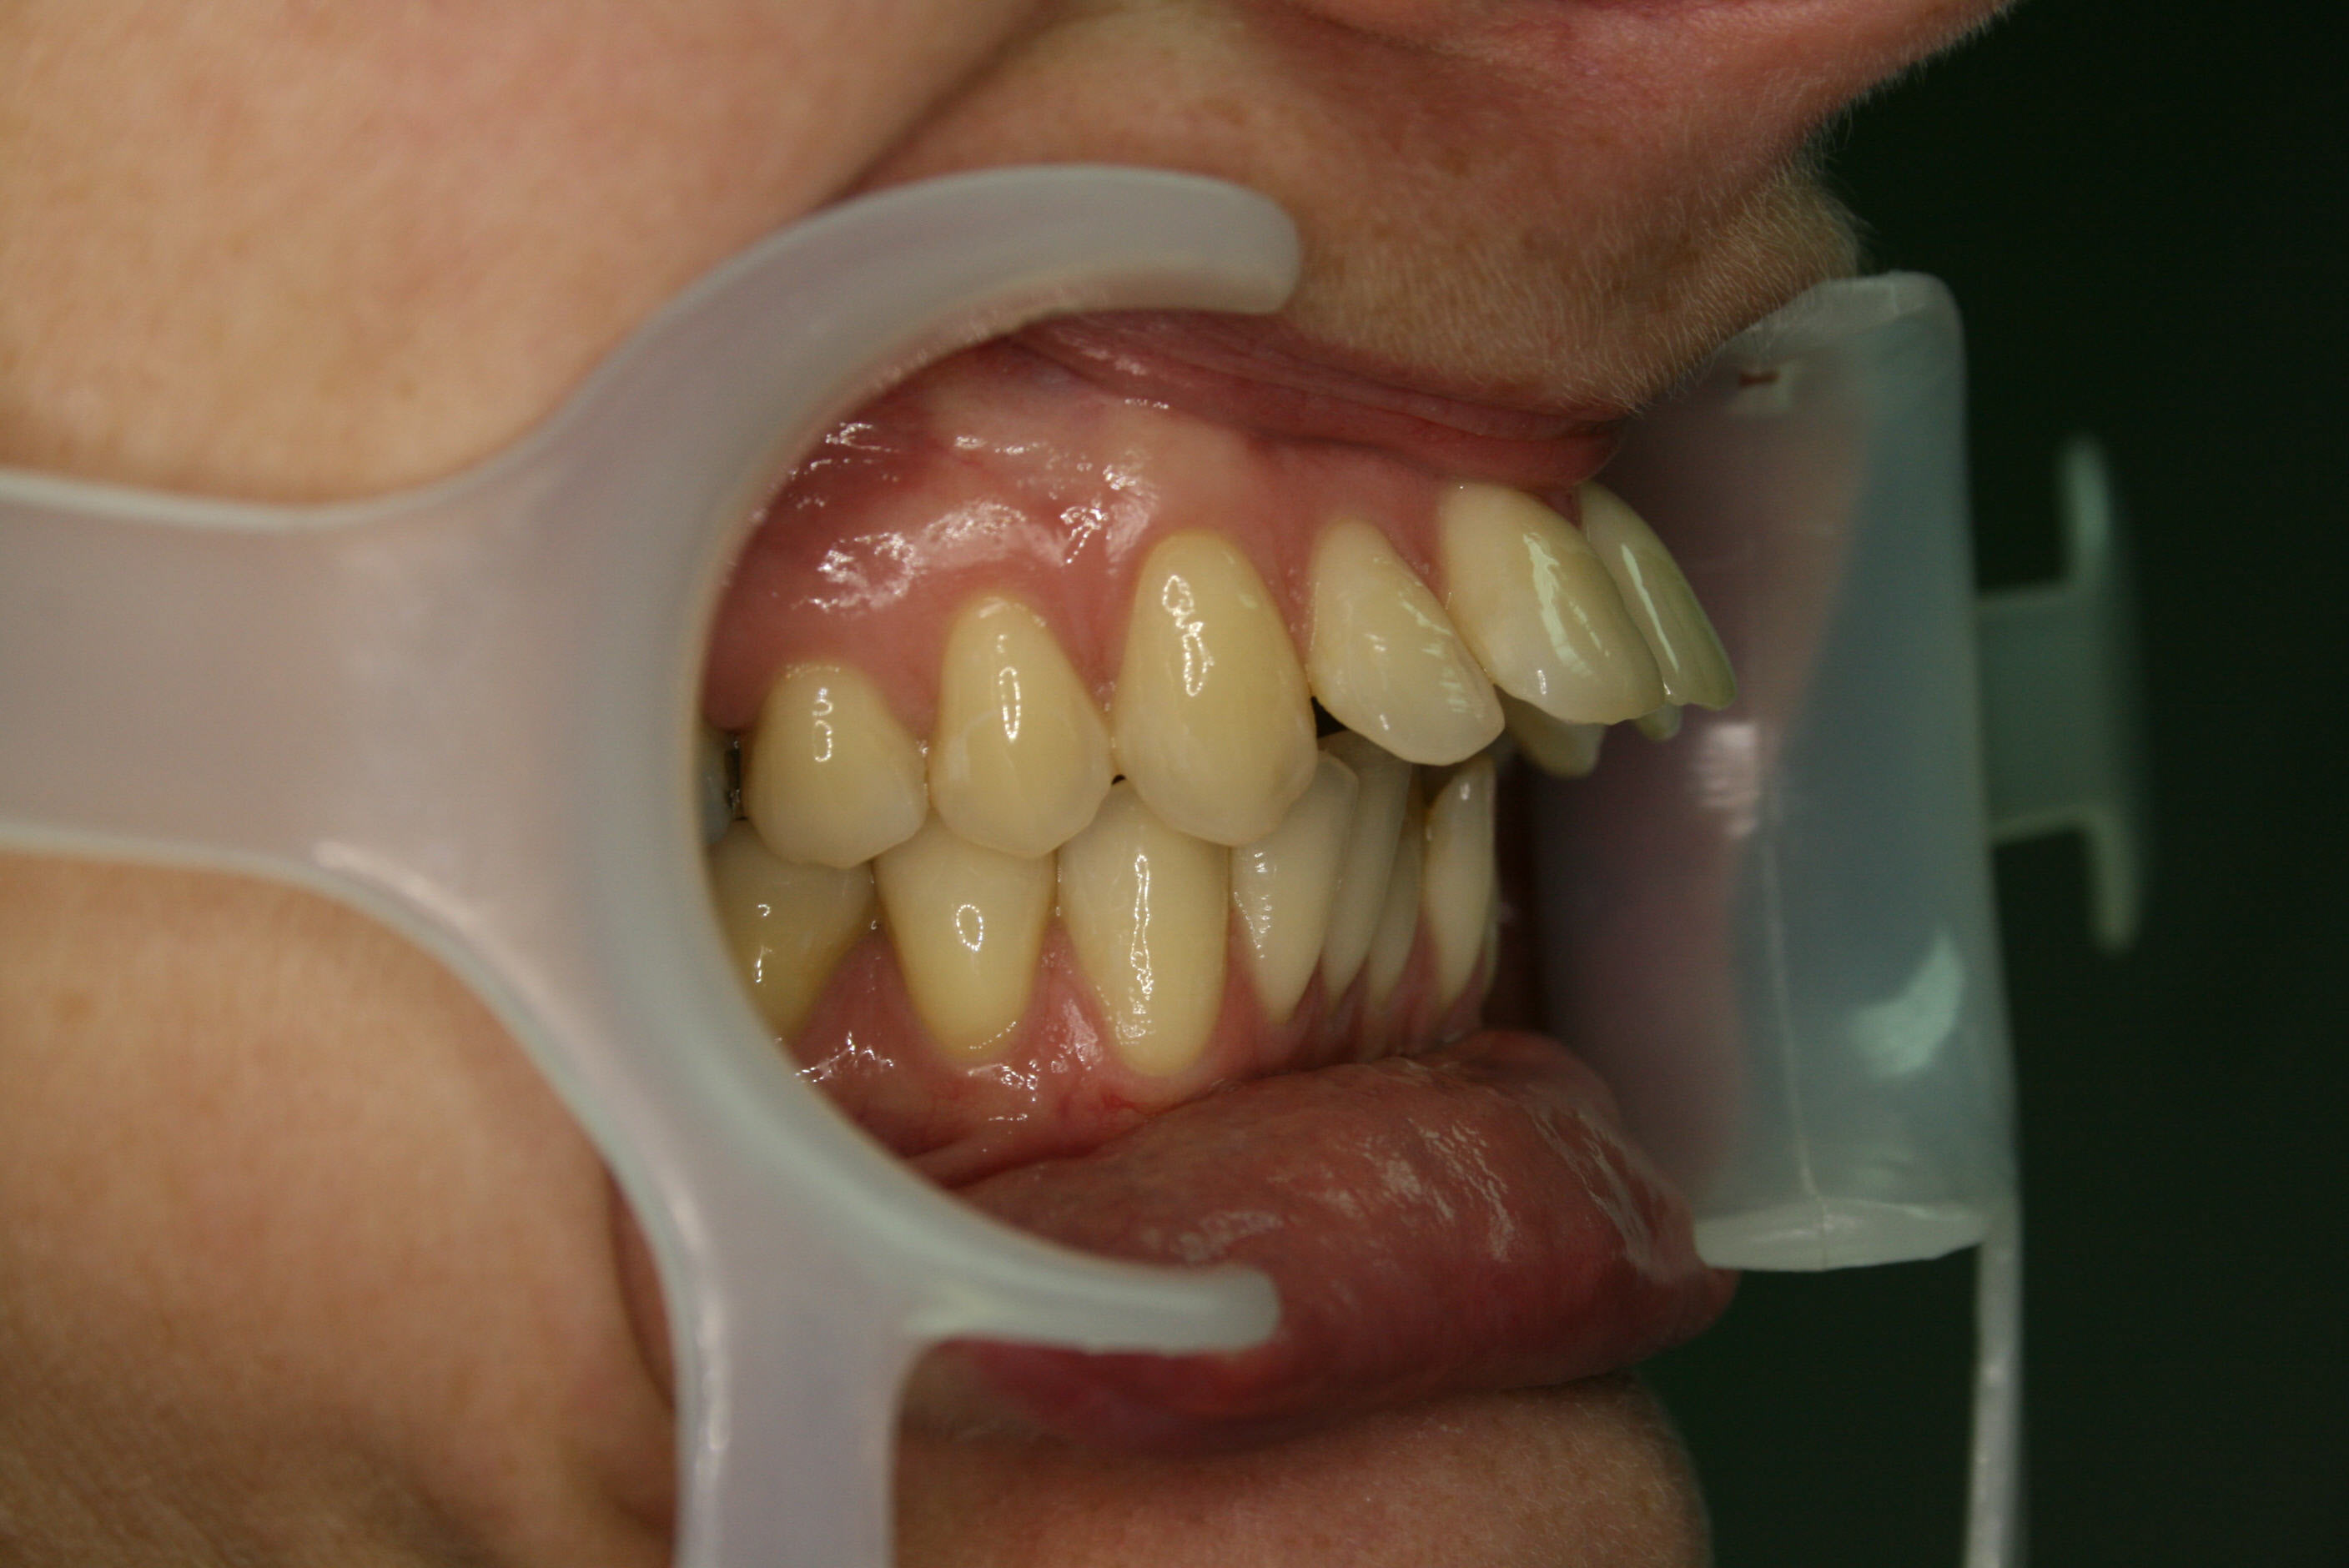

Vor der Behandlung

Lückenschluß in der Seitenansicht; hier ist gut zu erkennen, daß es gelungen war, den Lückenschluß von vorne her und achsengerecht auszuführen.